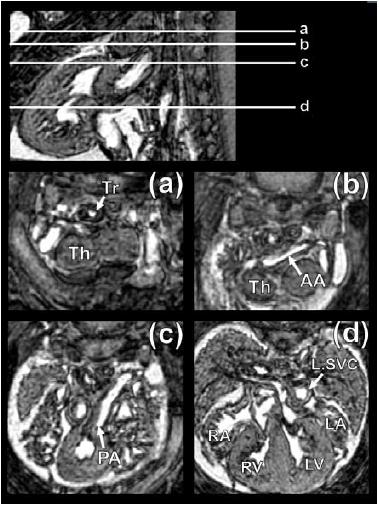

Cardiovascular magnetic resonance (CMR) imaging is the modality of choice for clinical studies of the heart and vasculature, offering detailed images of both structure and function with high temporal resolution.Small animals are increasingly used for genetic and translational research, in conjunction with models of common pathologies such as myocardial infarction. In all cases, effective methods for characterising a wide range of functional and anatomical parameters are crucial for robust studies.CMR is the gold-standard for the non-invasive examination of these models, although physiological differences, such as rapid heart rate, make this a greater challenge than conventional clinical imaging. However, with the help of specialised magnetic resonance (MR) systems, novel gating strategies and optimised pulse sequences, high-quality images can be obtained in these animals despite their small size. In this review, we provide an overview of the principal CMR techniques for small animals for example cine, angiography and perfusion imaging, which can provide measures such as ejection fraction, vessel anatomy and local blood flow, respectively. In combination with MR contrast agents, regional dysfunction in the heart can also be identified and assessed. We also discuss optimal methods for analysing CMR data, particularly the use of semi-automated tools for parameter measurement to reduce analysis time. Finally, we describe current and emerging methods for imaging the developing heart, aiding characterisation of congenital cardiovascular defects. Advanced small animal CMR now offers an unparalleled range of cardiovascular assessments. Employing these methods should allow new insights into the structural, functional and molecular basis of the cardiovascular system.

心血管磁共振(CMR)成像技术是心脏和血管临床研究的首选方式,能够以高时间分辨率提供心脏结构和功能的详细图像。越来越多的小动物被用于基因和转化研究,并与诸如心肌梗死等常见病理模型相结合。在所有情况下,有效表征各种功能和解剖参数的方法对于可靠的研究至关重要。CMR是这些模型无创检查的金标准,尽管诸如心率过快等生理差异使得这项工作比传统临床成像更具挑战性。然而,借助专门的磁共振(MR)系统、新颖的门控策略和优化的脉冲序列,尽管动物体型小,仍可在这些动物身上获得高质量图像。在本综述中,我们概述了用于小动物的主要CMR技术,例如电影成像、血管造影和灌注成像,它们可分别提供诸如射血分数、血管解剖结构和局部血流等测量值。结合MR造影剂,还可识别和评估心脏局部功能障碍。我们还讨论了分析CMR数据的最佳方法,特别是使用半自动工具进行参数测量以减少分析时间。最后,我们描述了当前和新兴的用于发育中心脏成像的方法,有助于先天性心血管缺陷的特征描述。先进的小动物CMR现在提供了无与伦比的一系列心血管评估。采用这些方法应该能够对心血管系统的结构、功能和分子基础有新的认识。